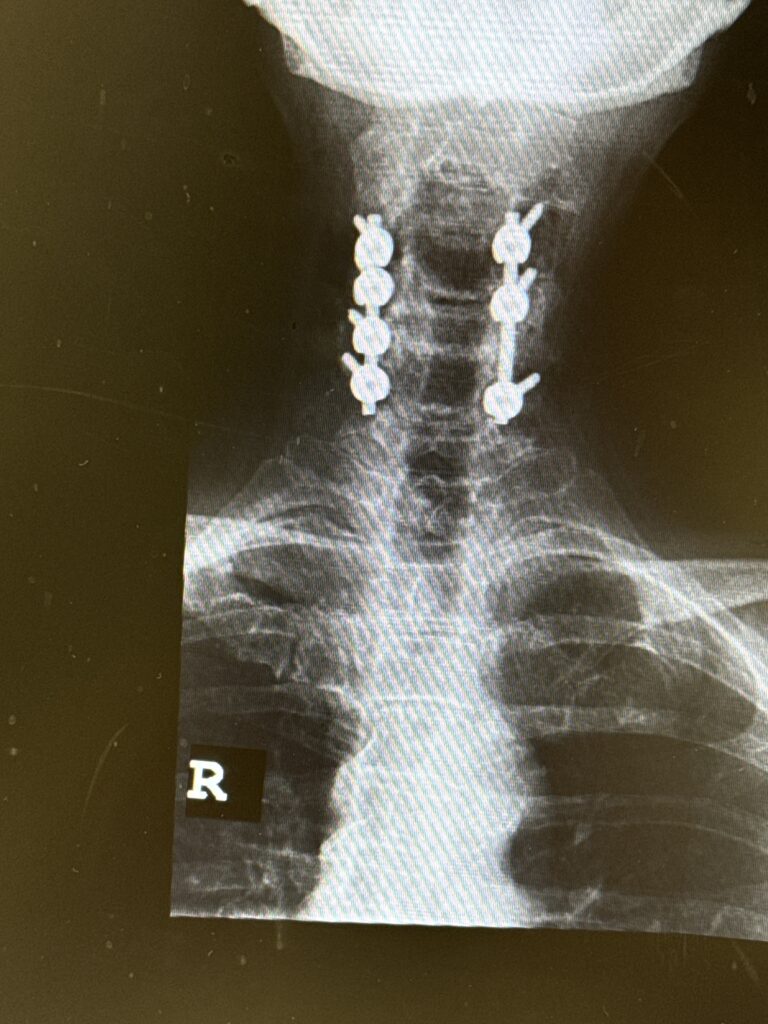

Another case was a 75-year-old female, who for about a year has had difficulties with her hands. She complained of numbness and weakness of her hands with some balance dysfunction. MRI revealed severe cervical stenosis, centered mainly at C4-C6 (Fig 4). There was both anterior and posterior contribution to the stenosis.

Although her upper cervical spine had a relative kyphosis, her mid and more inferior cervical spine curved into a more neutral to slight lordotic curve. Because she had significant degenerative collapse of her C4-6 segments anteriorly, and calcific compression anteriorly (Fig 5), it was decided to perform a posterior C3-C7 decompression of her spinal cord and a C3-C6 fusion with instrumentation to preserve her alignment (Fig 6).

We felt that the area of most concern could be approached posteriorly because the affected area of the cervical spine had a relative lordosis. A posterior approach to a kyphotic segment is not favorable because one can biomechanically worsen anterior neurological compression. It would be more difficult anteriorly because of her collapse of the disc space in order to get an adequate full decompression since she had significant posterior disease and compression. Because she had a relative lordosis a full decompression could be accomplished in our opinion better by a posterior approach.